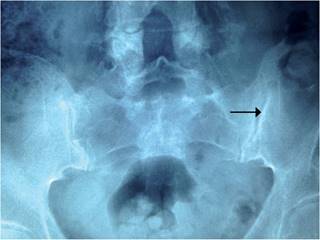

Por exacerbación de la sintomatología, acude a nuestra consulta en agosto de 2014. Al examen físico, se encuentra dolor y limitación acentuada a los movimientos de rotación de la columna cervical, pruebas de Schober, Gaenslin y Patrick positivas; sinovitis de rodilla izquierda con hidrartrosis y artritis de metatarsofalángicas derechas. La radiografía de pelvis muestra evidencia de esclerosis de la articulación sacroiliaca izquierda (Figura 1), y la RMN demuestra edema óseo de las articulaciones sacroiliacas (sacroileítis) (Figuras 2 y 3). El HLA-B27 resulta positivo. Se realiza artrocentesis e infiltración corticoidea de la rodilla afectada y se inicia tratamiento con celecoxib 200 mg cada 12 h, metotrexate 7.5 mg por semana vía oral y sulfasalazina 500 mg cada 8 horas, sin mejoría de la sintomatología después de 12 semanas de tratamiento. Por ello, se decide administrar etanercept 50 mg subcutáneo semanalmente, con notable disminución de la sintomatología articular a partir de la cuarta semana a la fecha, así como de los parámetros de laboratorio de inflamación, sin presentarse efectos adversos.